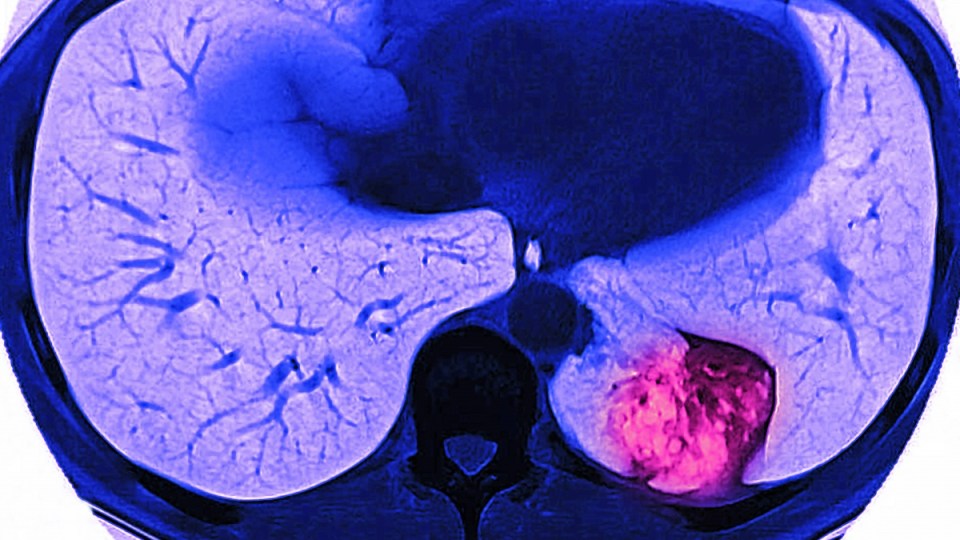

The IARC, whose findings were published in the journal JAMA Oncology on Thursday, says biomarkers could be a major help in identifying which smokers are most likely to benefit from lung cancer screening, such as low-dose radiation computed tomography (CT) scans.

Doctors can recommend people undergo low-dose CT scans to identify early tumours in the lungs.

However Professor Aranda said the CT scans can sometimes also lead to patients undergoing unnecessary biopsies because they pick up various types of nodules in the lungs that don’t always turn out to be harmful.